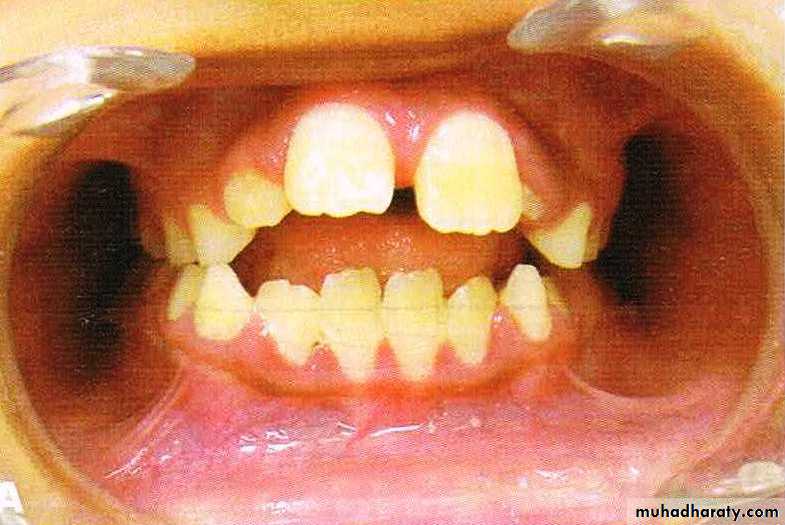

Angle’s class I malocclusion is characterized by the presence of a normal inter-arch molar relationship. The mesio-buccal cusp of the maxillary first permanent molar occludes in the anterior-buccal groove of mandibular first permanent molar.

The patient may exhibit dental irregularities such as crowding,spacing,rotations,missing tooth,etc.

Approximately 60%-70% of all cases of malocclusion fall into this class.